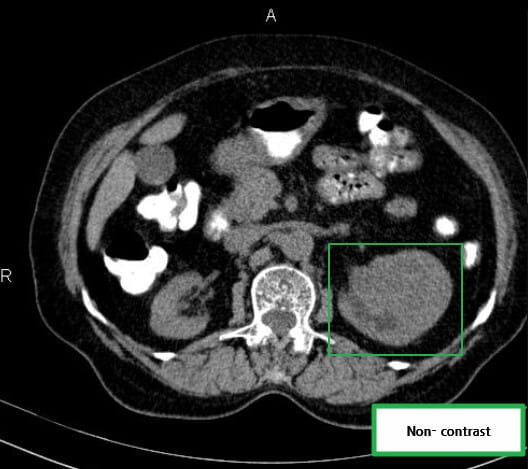

| 🔵 조영증강 CT (CT urography) |

| 가장 중요한 검사로, 고형성 종괴, 중심 괴사, 혈관 침범 여부 등을 평가합니다. 조영제 주입 후 비정상 조영 증강을 보이는 경우 악성 가능성 높습니다. |

영상소견 정리

CT/ MRI 소견

조영증강 영상에서 고형성 종괴 + 중심 괴사, 혈관 침범

| CT/ MRI 소견 |

| ✅ 조영증강 고형 종괴 |

| CT에서 조영제 주입 시 병변이 비정상적으로 밝게 조영되며, 실질보다 높은 밀도 |